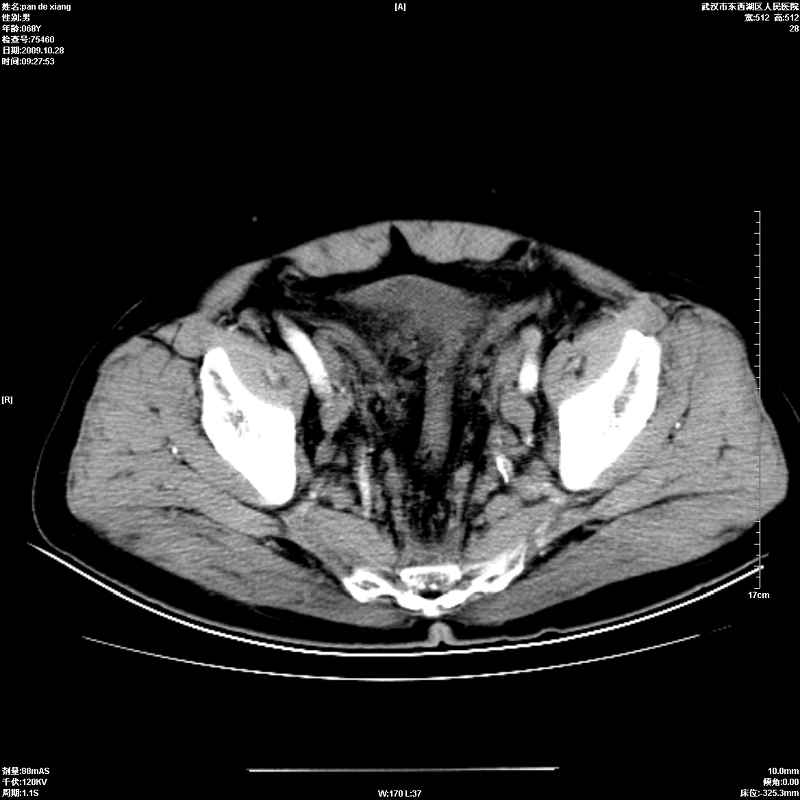

以下是引用杀毒软件在2009-10-28 20:41:00的发言:[br]结合临床考虑---白血病双肾改变或淋巴瘤。

以下是引用zxl51642在2009-10-29 9:59:00的发言:[br]结合临床“单克隆免疫球蛋白血症”,考虑双肾为继发损害并肾功能不全(尿中大量igg及少量iga、igm等大分子免疫球蛋白滤出所致继发损害),椎前软组织肿块为髓外造血。与浆细胞瘤有区别,平扫时有战友说的很清楚。